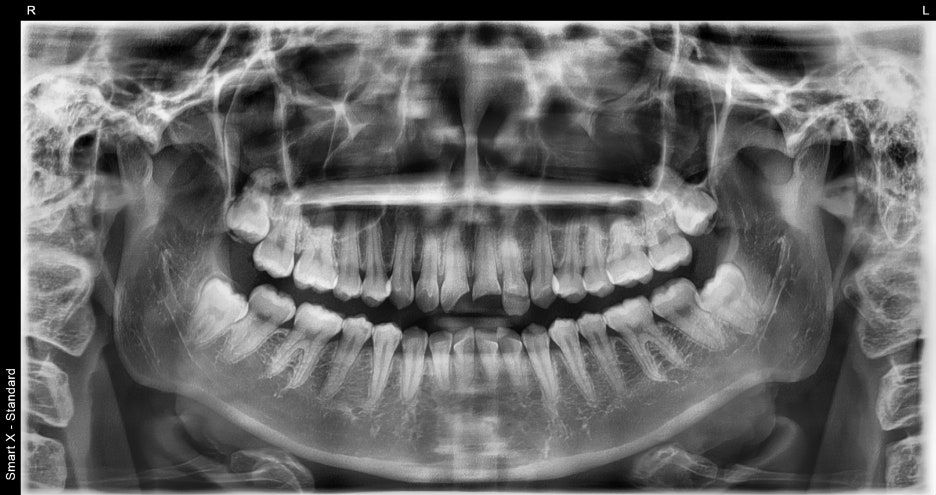

Diagnostic results

Fractures were confirmed in four maxillary front teeth.

Some teeth had exposed pulp and required root canal treatment,

and due to severe discoloration and fracture, we determined that

a crown restoration would be more appropriate than a simple resin restoration.